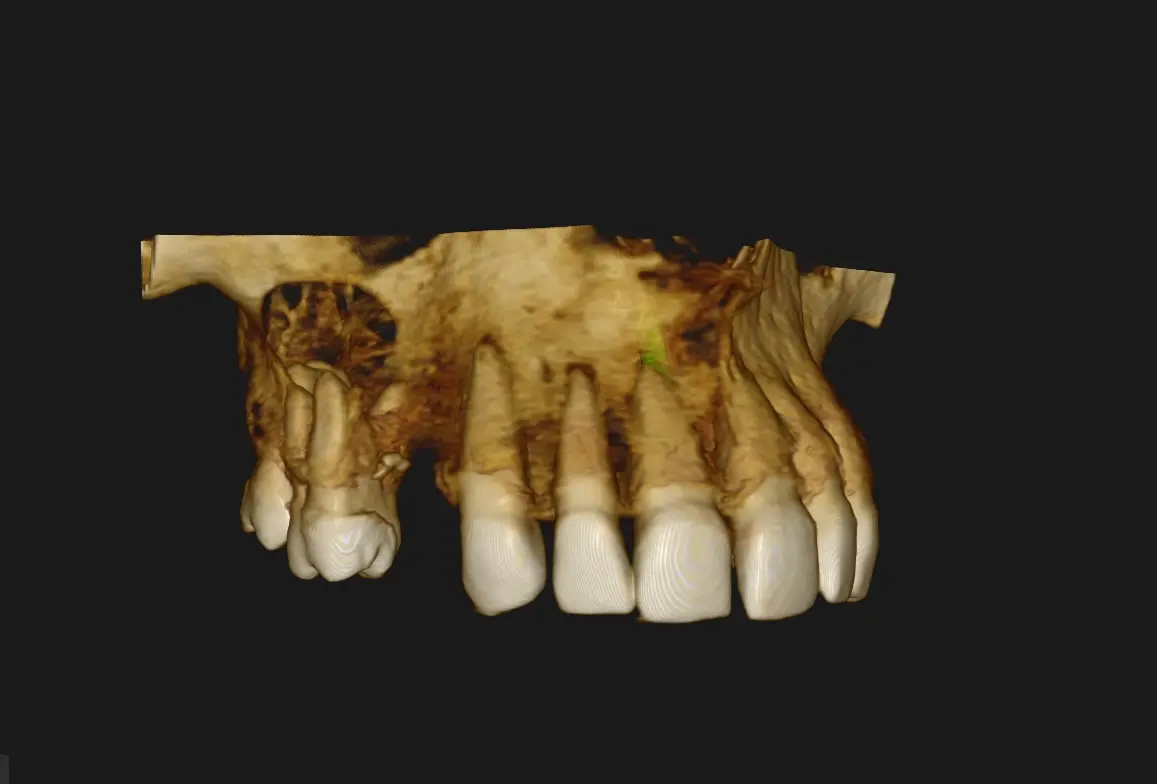

Al realizarle la tomografía se evidencia de manera general dientes con tratamientos de conductos que no llelgan al limite CDC (Ver imagen 1 panorámica). En zona de Pd 16 se ve imágen hipodensa , de carácter expansivo que empuja las zonas adyacentes y el seno maxilar, generando una disminución del reborde óseo tanto palatino como vestibular, se observa que la pieza dental 16 presenta tratamiento de conducto, esta lesión genera también un engrosamiento de la membrana sinusal (posible quiste de retención mucosa) y disminución o posible ausencia del piso sinusal. Sobre la misma se observa en la imagen N°6 que presenta los cortes trasnaxiales, una cavidad de aire en dicho quiste periapical. Posiblemente debido a una interacción con las bacterias sinusales. En la cavidad sinusal se observa el pólipo sinusal de la cavidad derecha.